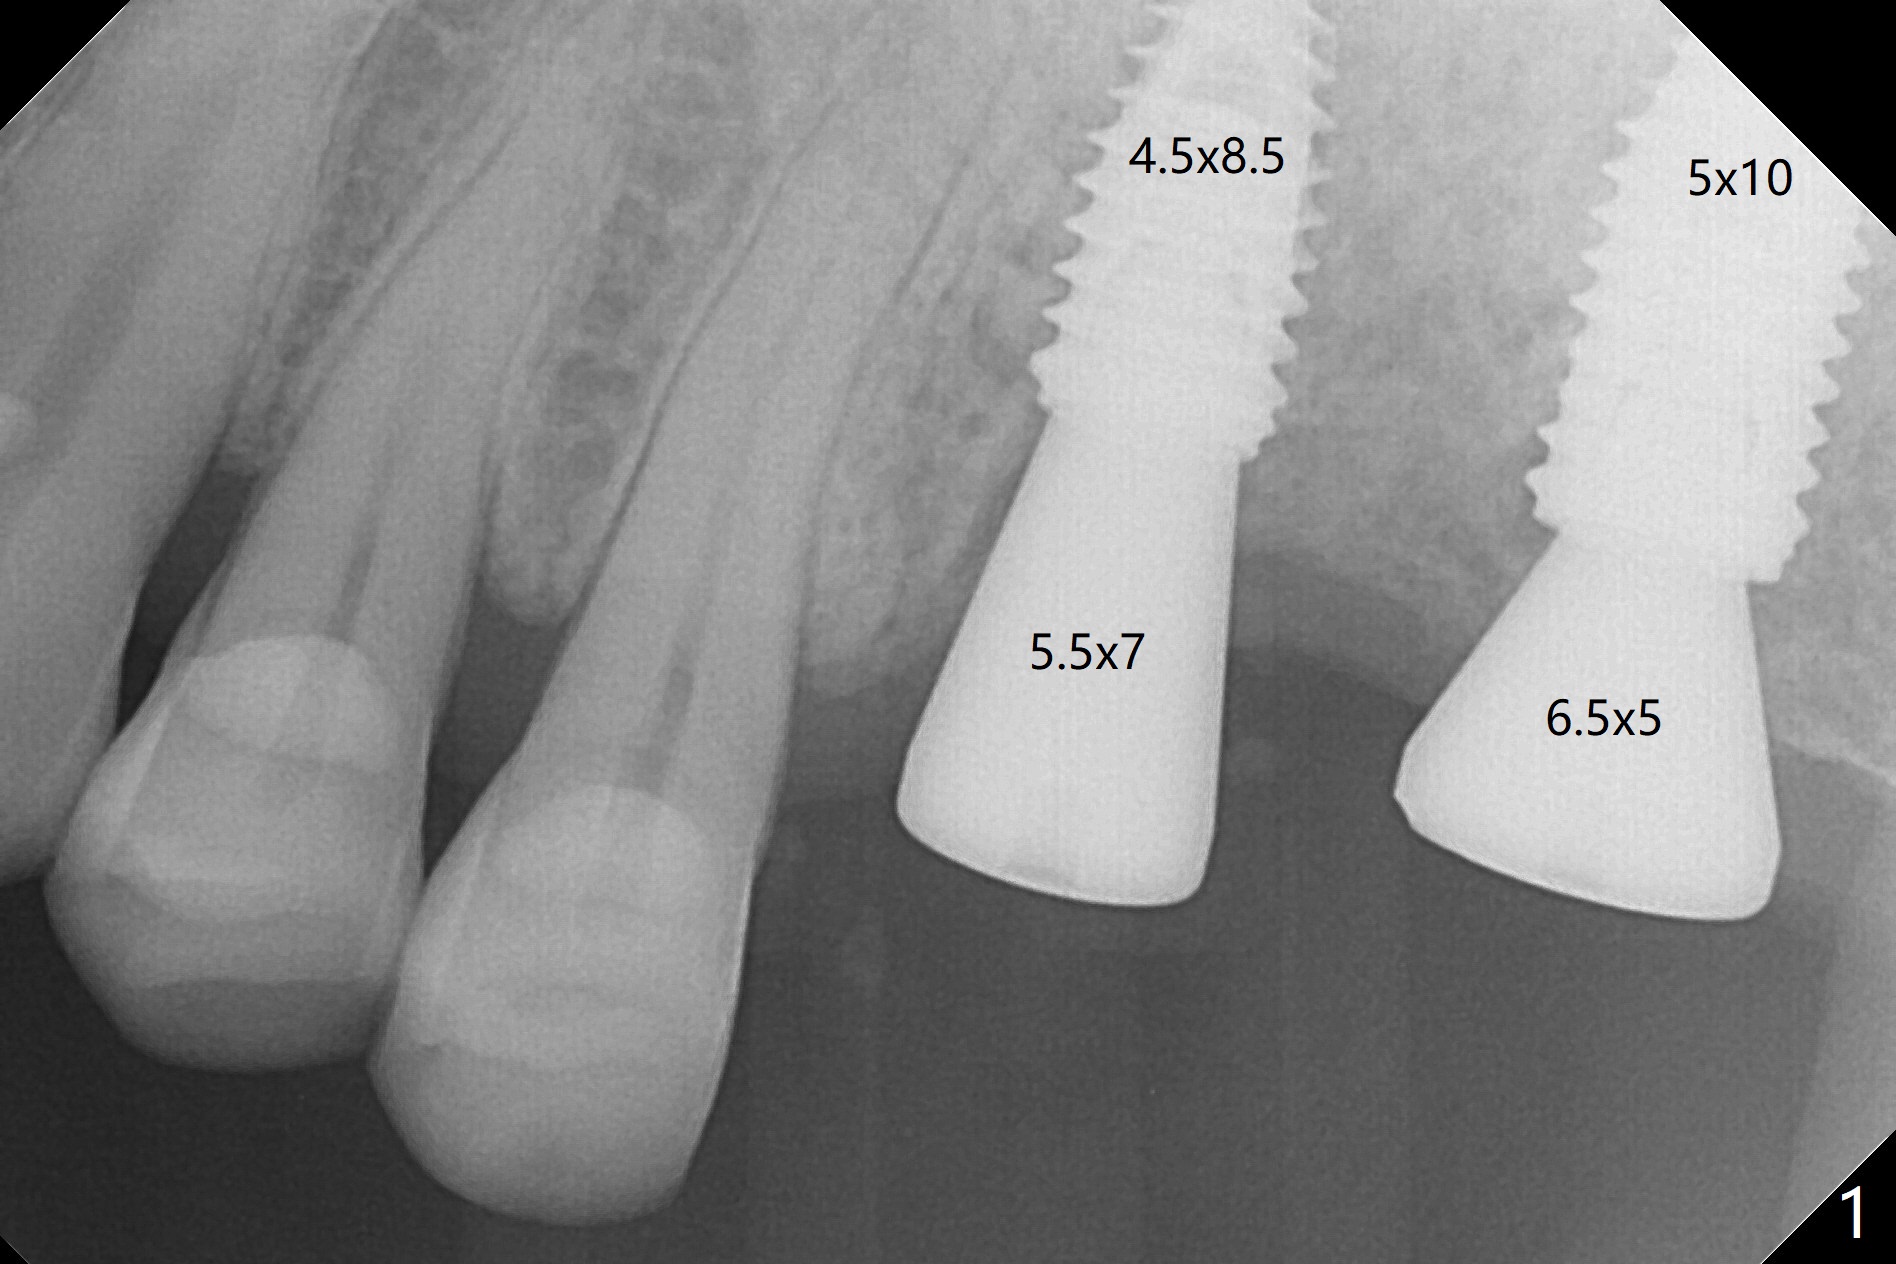

With one carpule of 2% Xylocaine with 1:100,000 Epinephrine, there is no intraop pain associated with placement of 2 implants with guide (Fig.1). Postop pain is minimal. Difficulty is high torque in insertion. At the site of #15, there is no bone shaving associated with 4 mm or less drills. The deeper portion of the bone seems to have denser bone. In spite of using 5 mm tap, which is not recommended, the insertion torque is so high that the implant has to be backed up several times before placement with ~ 50 Ncm. Bone profile is used at #14 before placement of a 5.5x7 mm healing abutment. The healing abutment at #15 dislodges 3 weeks postop and changes to a 5.5x5 mm one. No bone loss is observed 4 months postop (Fig.2). After failure to deliver crowns using impression coping, abutments are placed. The one at #15 is incompletely seated (Fig.3 <) probably due to the contact with the distal crest (*). Change to a smaller one results in complete seating (Fig.4). Cementation of the crowns with access holes is related to no residual cement (Fig.5).